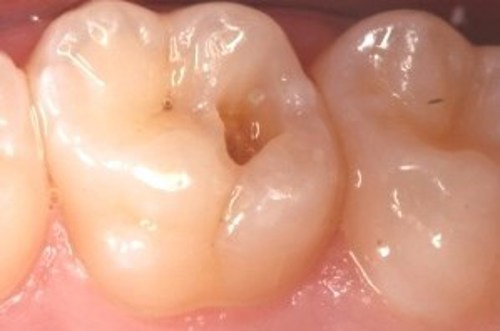

Hullet bliver lavet

Billederne nedenfor viser, hvordan hullet bliver lavet.

På første billede ses hullet som en sort plet på tanden.

På andet billede er tandoverfladen boret væk, så man kan se ned i hullet.

På sidste billede er hullet renset og der er lagt en plastfyldning i.